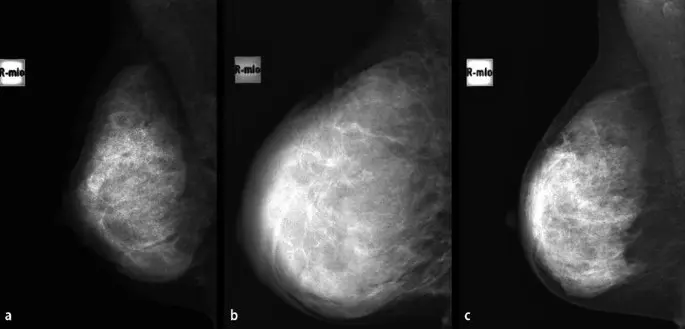

Während einer Schwangerschaft sind die Brüste aufgrund der hormonellen Veränderungen stark verändert. Das Brustgewebe ist dichter und die Milchdrüsen sind vergrößert. Diese Veränderungen können die Interpretation einer Mammographie erschweren und das Risiko für falsch-positive Ergebnisse erhöhen.